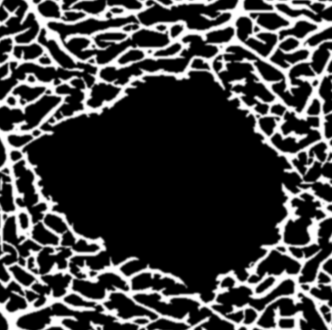

Our image segmentation is divided into three subtasks: the identification of small and big vessel and the FAZ. The final result, see Figure 2(b), is obtained by uniting the binary images with the small and big vessels and subsequently using the FAZ segmentation as a mask that excludes that area.

Refer to caption

(a) Original image

(b) Final segmentation

Figure 2: The combined substeps described in Sections 2.1 and 2.2 yield the final image.